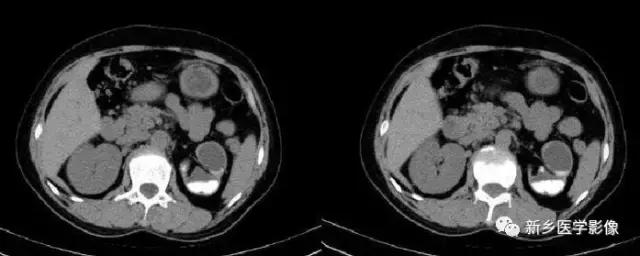

13、肾脏肿瘤

主要包括合并钙化的常见肿瘤或肿瘤样病变,如:肾囊肿,肾细胞癌,多房囊性肾瘤,多囊肝多囊肾囊壁钙化,肾脏结核,肾脏钙乳症。